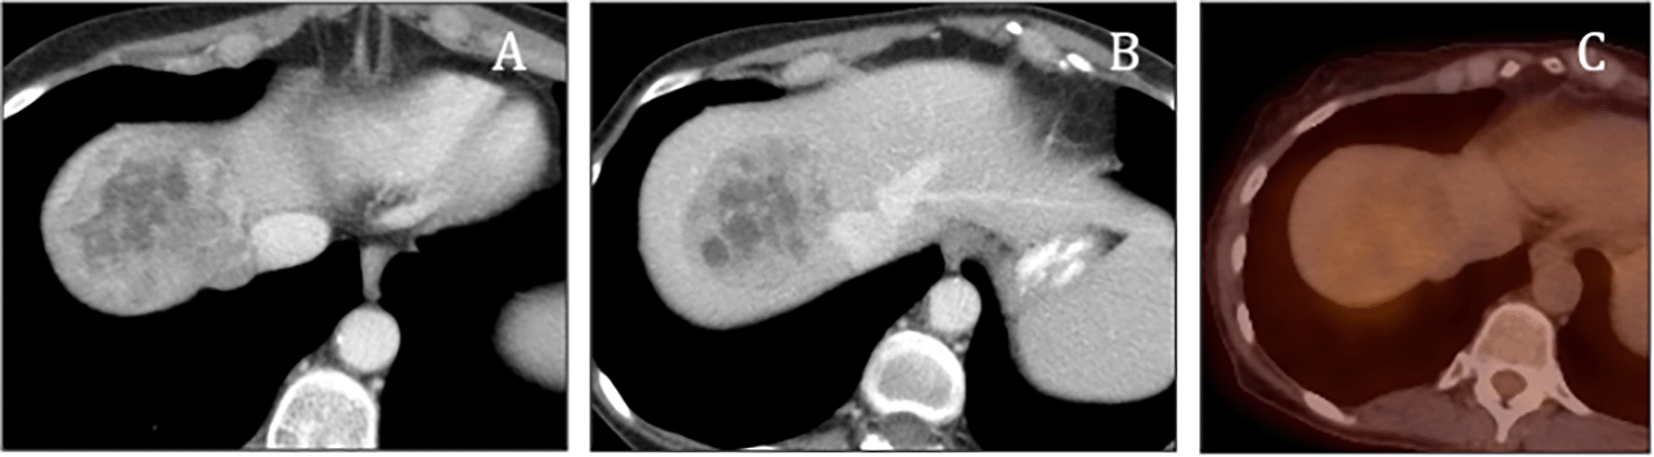

A computed tomography (CT) scan of the abdomen revealed a large, heterogeneous solid mass in the right lobe of the liver (Figure 1). Subsequent PET/CT imaging indicated mild activity in the hepatic mass (Figure 2). Laboratory evaluations demonstrated markedly elevated levels of urinary metanephrines, with total metanephrines measured at 10,211 mcg/24 hours (urinary metanephrines at 3,375 mcg/24 hours and urinary normetanephrine at 6,836 mcg/24 hours). Additionally, her blood norepinephrine level was found to be 702 pg/ml. During the surgery, a diaphragmatic paraganglioma was discovered and subsequently resected (Figure 3).